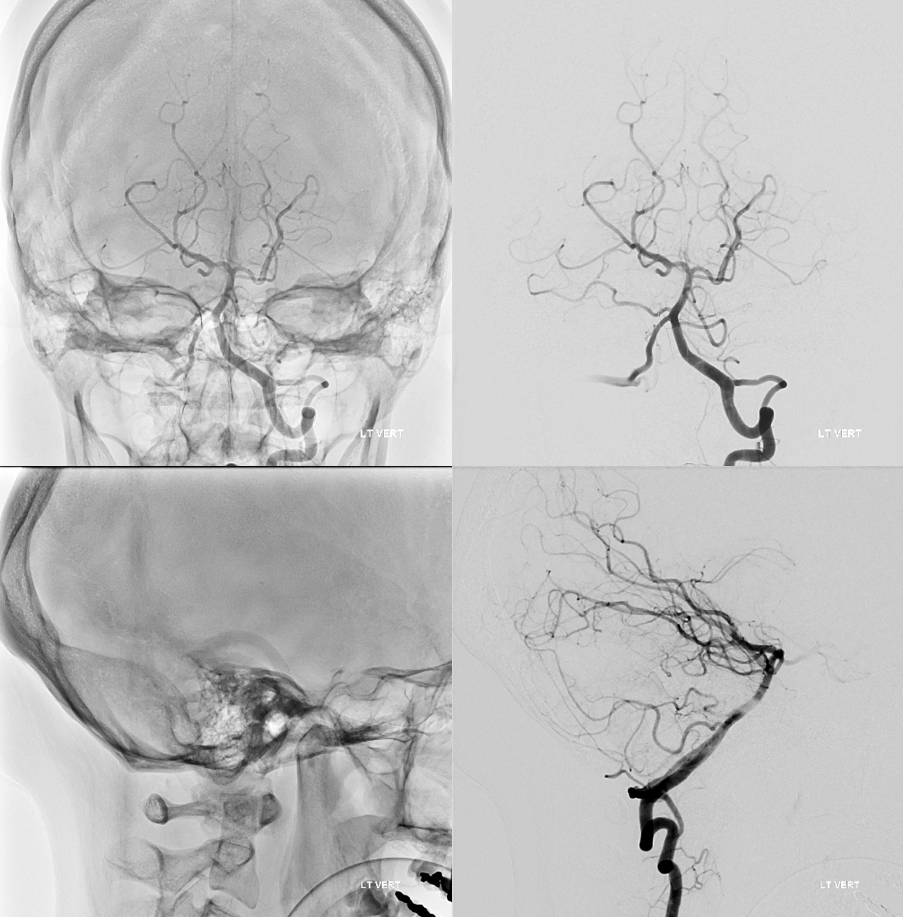

Bilateral vertebral artery study in anterior spinal artery supply

Left vertebral (top) and right vertebral (bottom) set of images from the same patient, demonstrating full length of cervical anterior cerebral artery supply from the vertebral system. The lower portion of the cervical ASA (red) is fed via the left C5/6 radiculomedullary contributor, which also happens to supply the posterior spinal artery network (purple). The upper ASA segment is fed by the right C4/5 radiculomedullary artery seen on the image below. The radicular portion is labeled in yellow. ASA=red; Posterior spinal arteries = purpleÂ